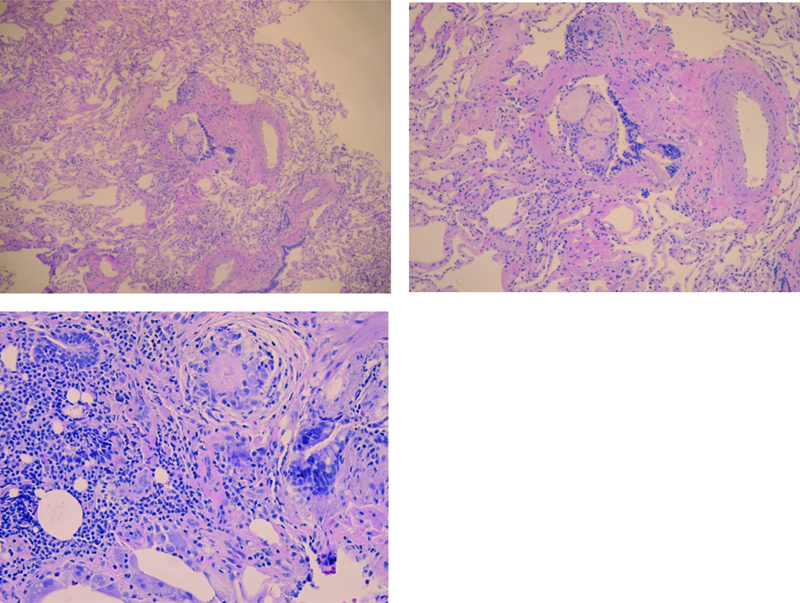

Figure 3

Figure 3. Images (power 5x, 10x & 20x) show lung parenchyma with foreign material (starch; lentil) in the bronchiole with associated foreign body giant cell reaction.